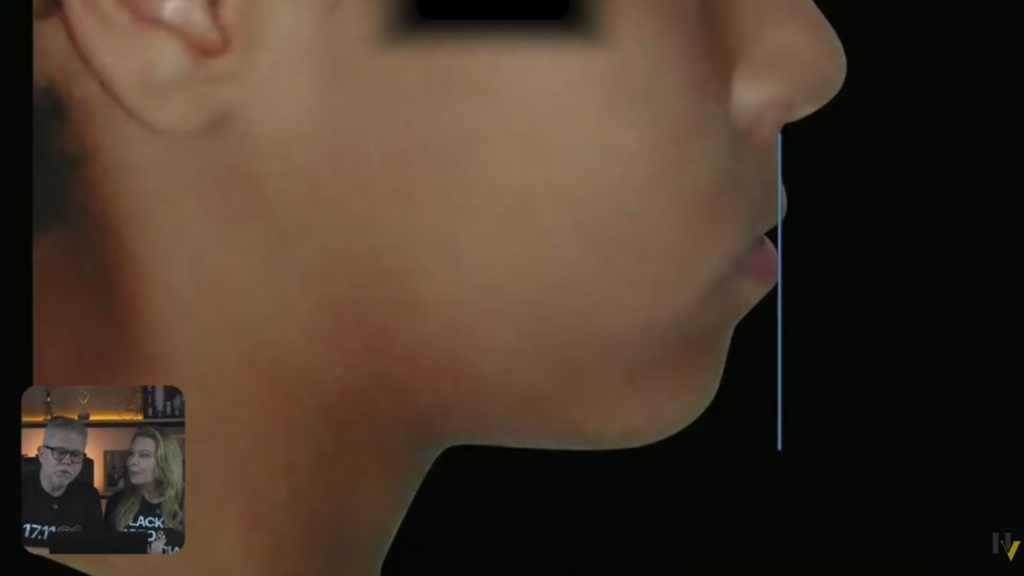

A gente está percebendo aqui que esse paciente, olha a face dele:

Aparentemente é um paciente normal.

Ele pode até ter ali uma linha que é o pescoço um pouquinho maior, mas eu não vejo tanta diferença.

Está bonita a face dele.

Então quando a gente olha:

O paciente está com a face bonita;

O paciente ficou de topo a topo na hora que manipulou:

Então já tem dois fatores aí que são muito favoráveis.

E esse paciente foi tratado de forma muito tranquila e ficou dessa forma aí:

Muito tranquilo, um caso de inclinação de incisivos, não era padrão 3, não era classe 3.

Ele tinha apenas uma mordida cruzada anterior.

A face dele, dá para ver a linha queixo-pescoço estava no tamanho normal, até para diminuída

Agora, depois do tratamento, quando ele era menor, a linha queixo-pescoço estava até normal, um pouquinho aumentada.

Mas por quê? Por causa da postura dessa mandíbula à frente. Então, tomem muito cuidado com isso!